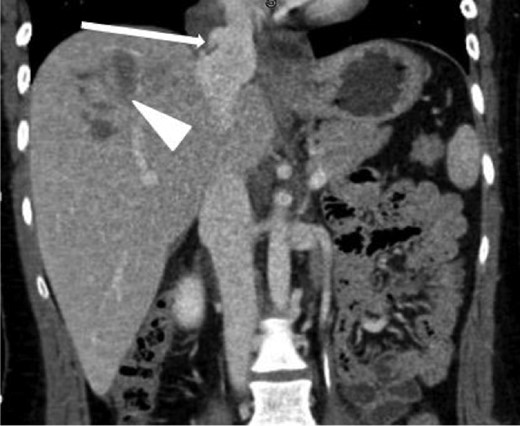

A 20-year-old female was the restrained driver of a vehicle traveling ∼45 miles per hour when her vehicle crashed into a city bus. She was extricated on scene by emergency responders and brought to the trauma bay alert, oriented and in stable condition complaining of pain on deep inspiration as well as left leg pain. She denied any abdominal pain or light-headedness. Vital signs on arrival were heart rate of 115 bpm, respiratory rate of 20 breaths per minute and blood pressure of 101/76 mmHg; her Glasgow coma scale was 15. The initial chest radiograph showed a small, right-sided pneumothorax and pulmonary contusions. Two radiographic views of the left leg revealed comminuted, mildly displaced tibia and fibula fractures. Computed tomography (CT) scans of the brain and neck were unremarkable. A contrast-enhanced chest CT scan demonstrated non-displaced right lateral second and third rib fractures, right upper lobe pulmonary contusions with laceration and a small pneumothorax, partially visualized grade 5 liver laceration with active contrast extravasation, and an acute, traumatic supradiaphragmatic IVC injury with an associated moderate hematoma and contrast extravasation that appeared to be contained, as seen in Figs 1 and 2. In view of incompletely imaged critical findings of the upper abdomen and continued hemodynamic stability of the patient, a dedicated abdomen and pelvis CT scan, seen in Figs 3–5, was performed 20 min later, which showed a stable 1.3 cm pseudoaneurysm of the supradiaphragmatic IVC without extension into the pericardium, stable moderate pericaval hematoma surrounding the injury, stable grade 5 liver laceration and a trace amount of fluid in the peritoneal cavity. A liver transplant surgeon and a cardiovascular surgeon were consulted due to the presence of acute traumatic suprahepatic IVC pseudoaneurysm.

Coronal contrast-enhanced CT of the chest showing abnormal contour of the supradiaphragmatic IVC with ventrally and laterally confined contrast extravasation (arrow) consistent with a pseudoaneurysm surrounded by pericaval hematoma as well as a segment 8 hepatic hypodensity consistent with liver laceration and focal area of contrast extravasation (arrowhead).

Coronal contrast-enhanced CT of the abdomen performed 30 min after the initial CT of the chest showing persistence of the abnormal contour of the supradiaphragmatic IVC with contrast extravasation confined laterally and ventrally (arrow), nonexpanding pericaval hematoma and a segment 8 hypodensity (arrowhead) consistent with liver laceration.